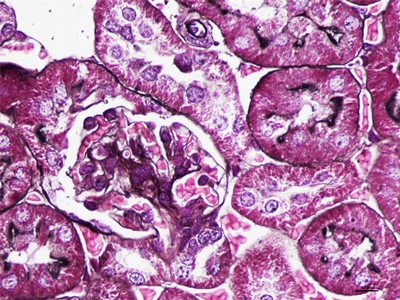

HE染色简称苏木精是是一种由碱性染液苏木精和酸性染液伊红构成的一种染色方法。是通显微镜下观察病理切片里病变的组织学形态变化来诊断疾病的,适用于胚胎学、病理学,生物医学,病理学教学与科研。HE染色对碱性染料和酸性染料亲和力都比较弱的现象称为中性。组织切片苏木素染色、分化与反蓝:将水化后的组织样本的切片使用PBS溶液浸泡清洗,每次浸泡5min,总共清洗3次。之后用移液枪吸取已经预先配置好的苏木素染色液,每个组织切片滴加100ul,充分染色10min。切片经HE染色后,要彻底脱水透明,才能用黑龙江中性树胶封盖。he染色对于贴壁生长细胞,胰酶消化,调整细胞浓度约1×105/ml,滴加于盖玻片上(置于6孔板中),培养相应时间后,取出细胞爬片,用PBS 洗涤3次。着色情况与组织或细胞的种类有关。切片在苏木素染液中停留过长;或切片太厚;或分化时间太短。这种情况首先镜下看看切片厚度(最佳厚度1-2层细胞核),要么重新染色,要么重新制片。染色的最终结果是:细胞核呈蓝色、胞质、肌纤维、胶原纤维和红细胞呈深浅不一样的红色,病理技术服务提醒:在进行HE染色需要染色时间,脱水,染色时间不一样,需要等 ,明确HE评判标准。